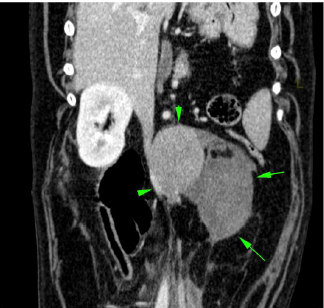

Im CT kann der Tumor bestätigt werden, bei der beobachteten Flüssigkeit handelt es sich um Blut. Eine Gewebepunktion diagnostiziert ein sogenanntes Phäochromozytom - ein Tumor der Nebenniere, welcher aus Zellen besteht, welche das Hormon Adrenalin produziert.

Phäochromozytome können in die hintere Hohlvene einwachsen, was die Entfernung massiv erschweren oder verunmöglichen kann. Bei Maylo wurde offensichtlich durch das Tumorwachstum ein Gefäss beschädigt, welches blutete und zum beobachteten Hämatom (Bluterguss) führte. Es ist denkbar, dass diese Blutung auch für die akuten Bauchschmerzen des Hundes verantwortlich war.